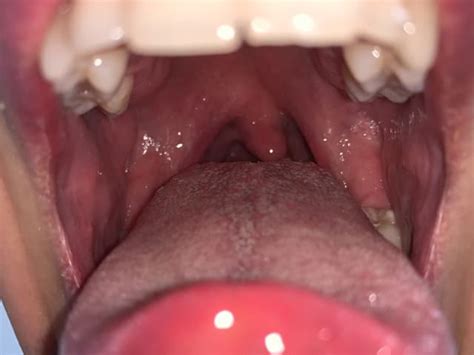

What Do Inflamed Tonsils Look Like

Curious about what the tonsils do? Discover the vital role these lymphoid tissues play in your immune system, acting as a first-line defense against pathogens. Learn how they trap bacteria and viruses to prevent infections, their function in oral health, and when issues like tonsillitis might require professional medical attention to maintain your overall well-being.